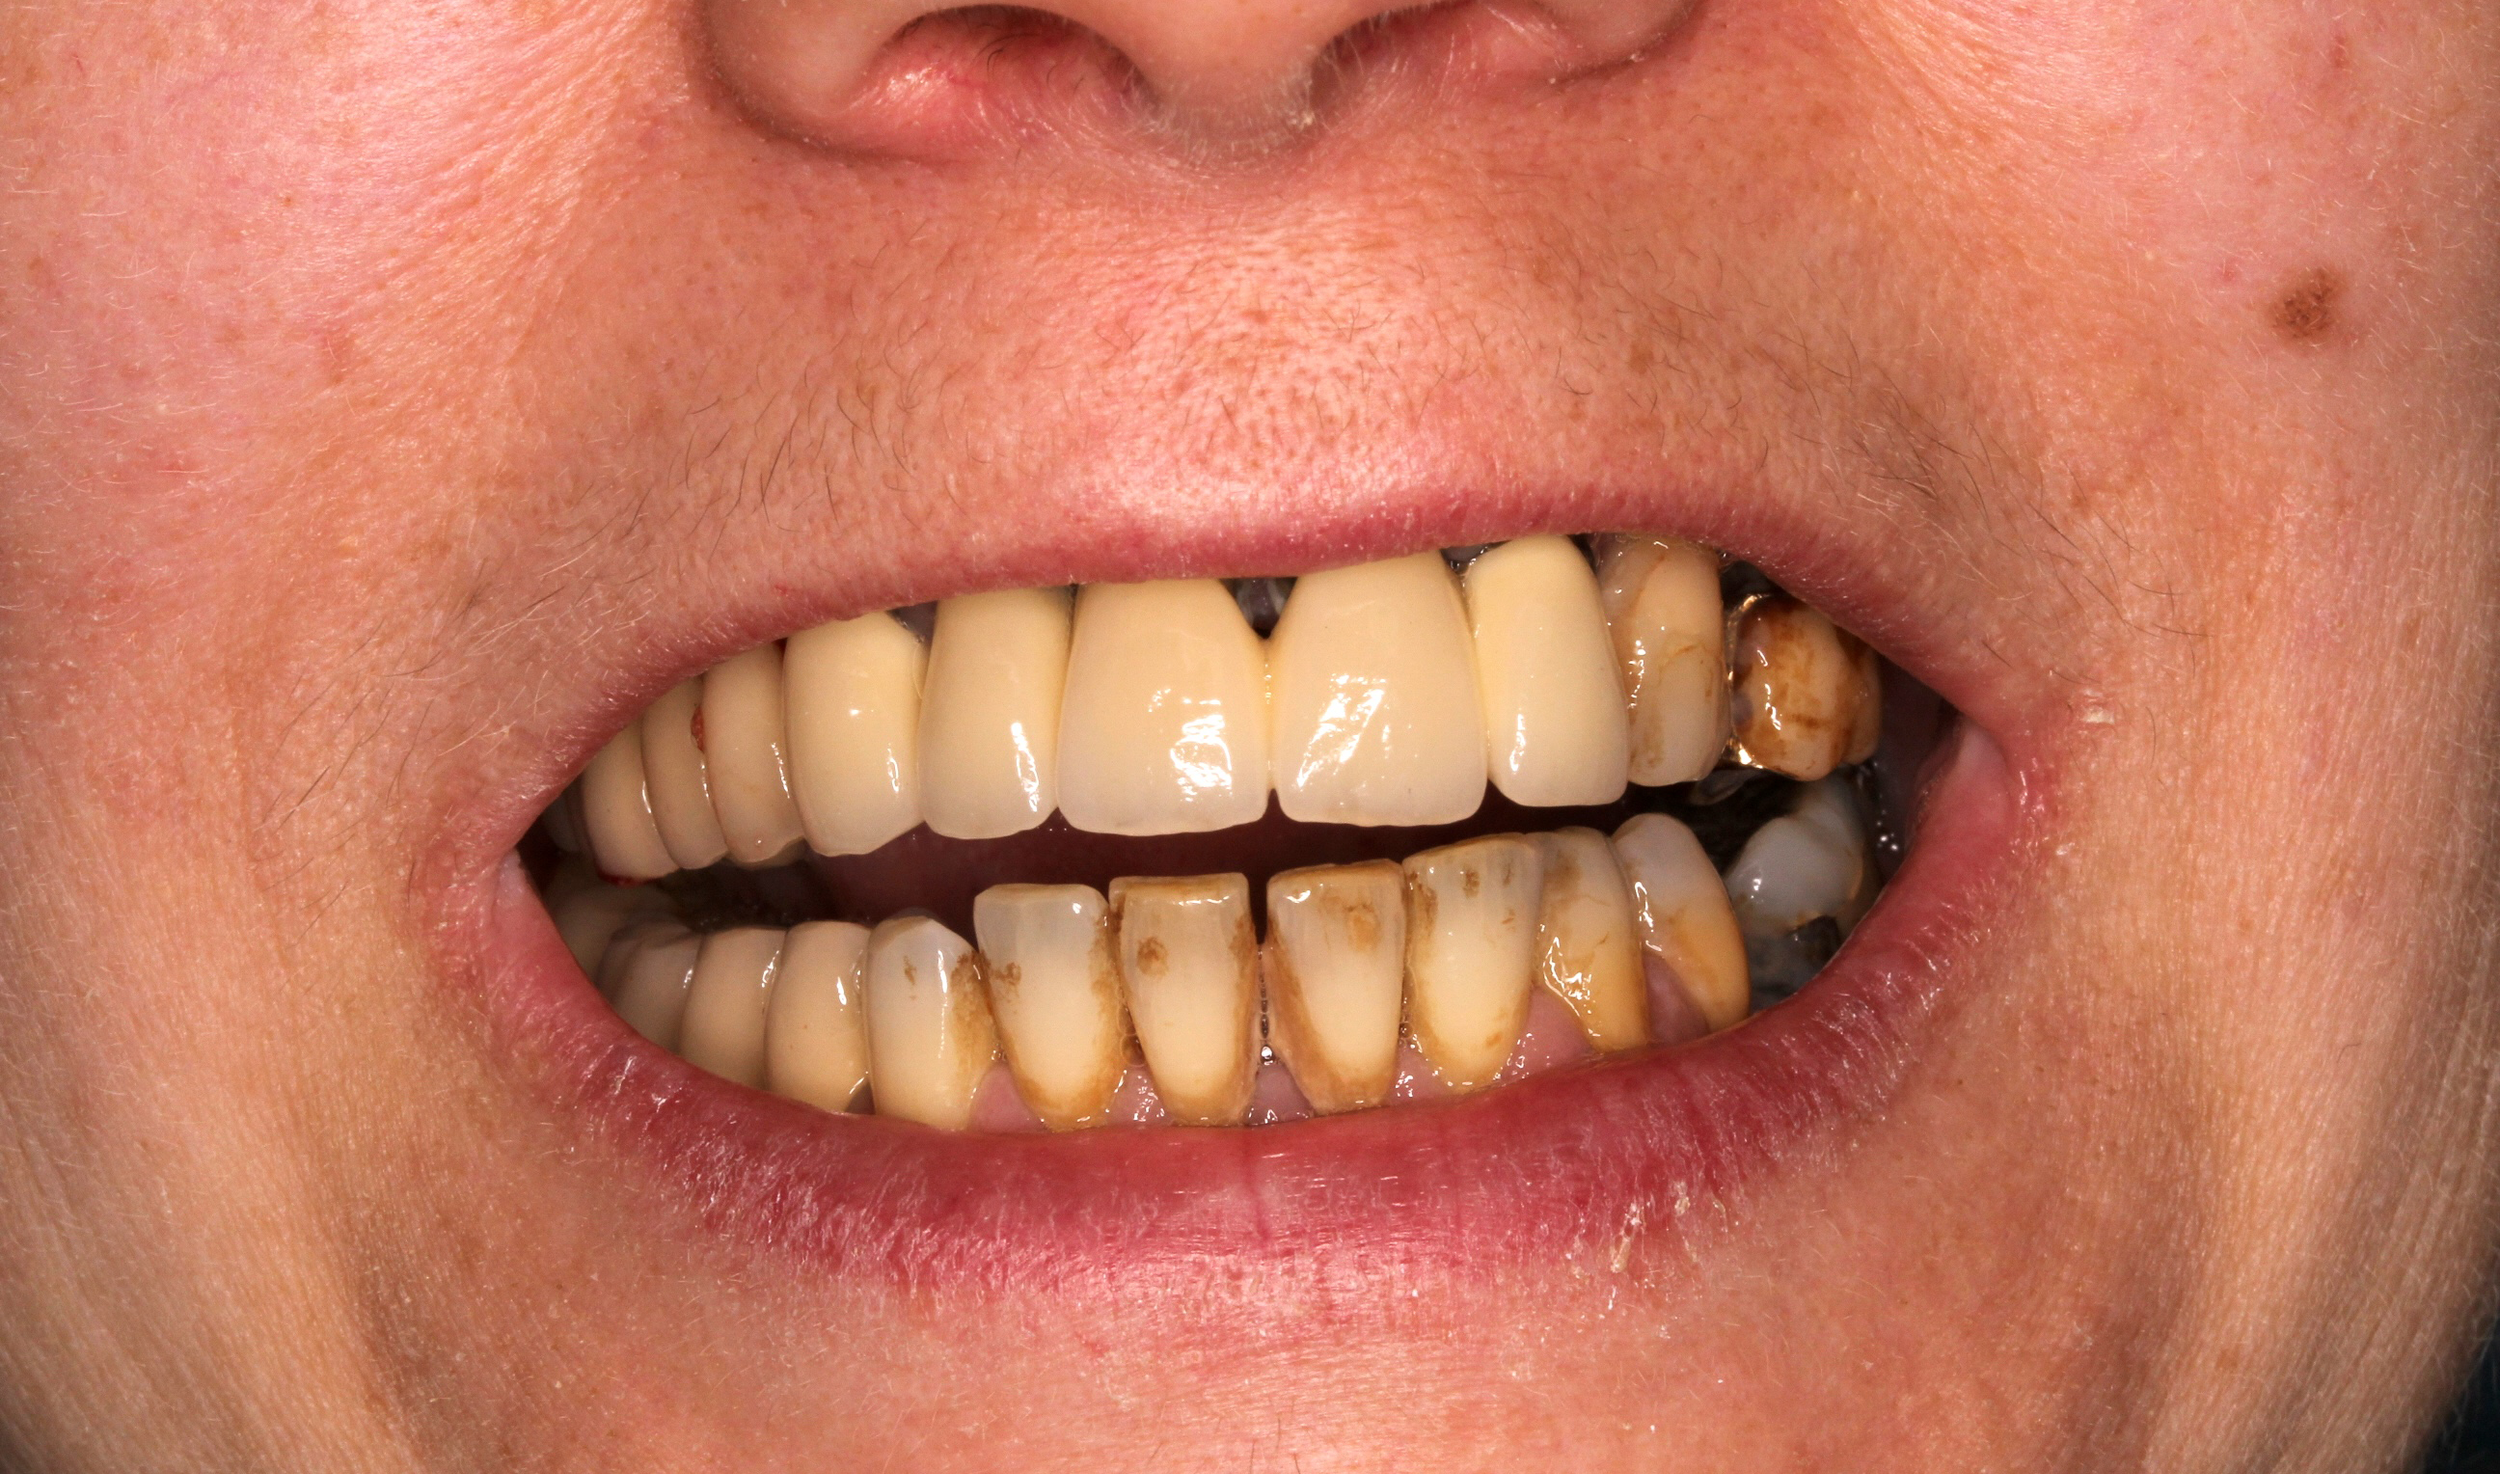

Caso 1

La paziente ha subito un trauma sugli elementi frontali nel 2000. I denti sono stati recuperati e riabilitati protesicamente con corone fisse sulle radici naturali. Dopo più di 20 anni, l’elemento 11 mostra segni di riassorbimento radicolare (tipico dei denti traumatizzati). Si procede con la sostituzione dell’elemento con un impianto singolo.

PRIMA